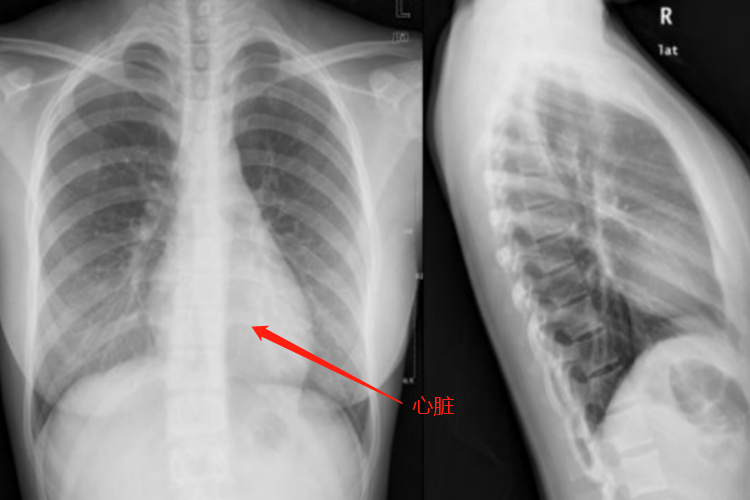

正常胸透图片是由黑、白两种颜色组成,通过黑、白颜色分布来进行观察。如分布在两边好大一片黑色,犹如一扇窗户的位置为肺,由于它能让X线透过,所以在胸片上呈现出黑色。在两肺之间夹杂着一大片白色,此处为心脏,医学上把这一带叫作纵隔,其中有心脏、大血管、气管等。由于它们密度大,致使X线无法透过,或是透过的X线较少,因此在胸片上呈现出白色。

但多是黑、白跌倒则预示疾病,如该黑的地方变白了,或是该白的地方变黑了,这就是异常。前者常见的有炎症、结核、肿瘤、胸腔积液等,后者有肺气肿、气胸等。